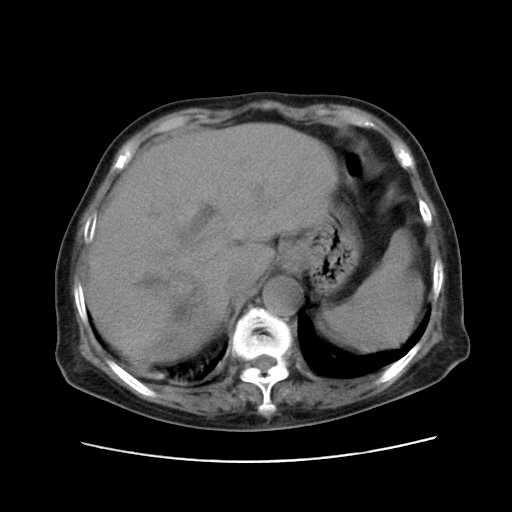

标题: CT25203:上腹部增强,看看

女,77.无不适

肝脏变异、异位胆囊,肝右叶肝内胆管结石并肝内胆管扩张。

肝右叶肝内胆管结石并肝内胆管扩张。

肝右叶肝内胆管结石并肝内胆管扩张。胆总管下段梗阻,考虑壶腹部占位。

右侧肝内胆管局限性扩张,其内密度不均匀,扩张的胆管壁增厚,考虑肝内胆管炎合并结石可能性大